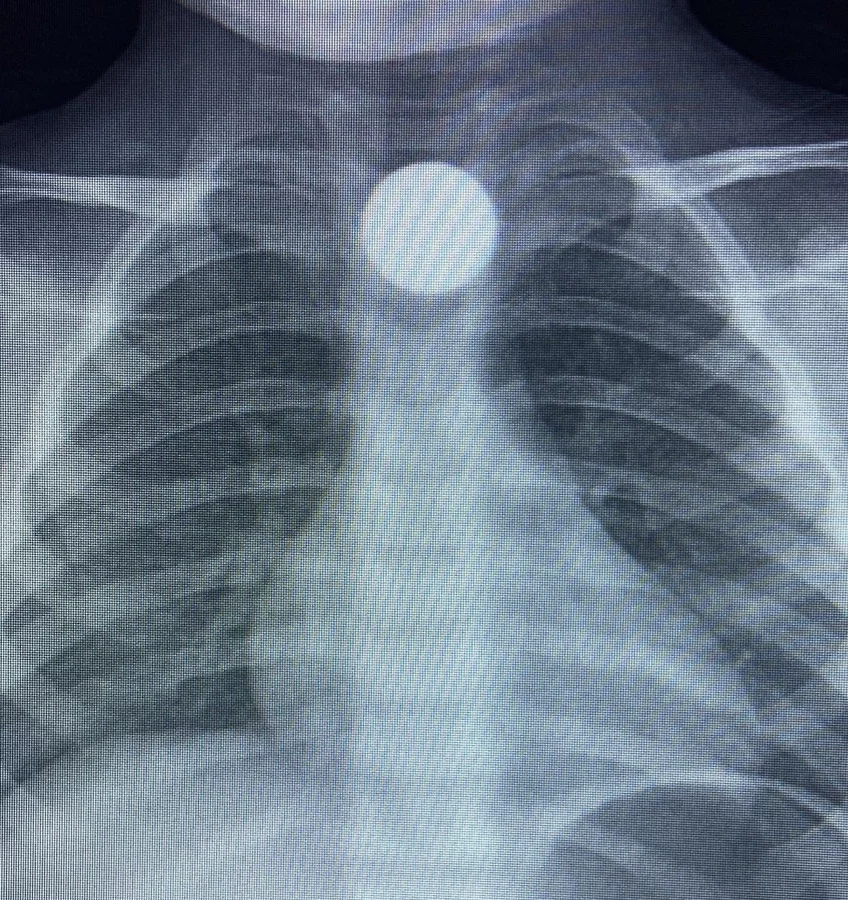

Yapılan tetkiklerde yemek borusunda takılı kalan madeni para görüldü.